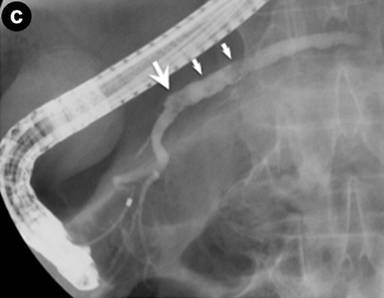

Following the diagnosis of autoimmune pancreatitis, screening CT images demonstrated pelvic lymph nodes that gradually increased in size (about 1.5 cm) and number. In June 2009, following CT detected an ill-enhanced hepatic tumor (Figure 3a). Endoscopic examinations denied upper and lower gastrointestinal tumors that could be the origin of hepatic tumor. Various candidates were considered, such as pseudotumor, cholangiocarcinoma, hepatocellular carcinoma, hepatic adenoma and metastasis of past bladder cancer. Percutaneous needle biopsy was performed to reach a final diagnosis. Histology of the biopsy tissue was urothelial carcinoma (Figure 3b), the same as in the bladder resected 5 years and 6 months previously (Figure 3c). The patient refused a second operation. Chemotherapy with gemcitabine was initially effective, but failed in one year, and metastasis developed in the adrenal gland, paranasal sinuses, and cervical vertebrae. Second line therapy by paclitaxel was not effective and the patient succumbed in January 2011.

Figure 3. Hepatic metastasis of the bladder cancer. a. CT showed an ill-enhanced, round-margined, tumor in the right lobe of the liver (arrow). b. Histology of percutaneous hepatic biopsy showed urothelial carcinoma, the same as that of urinary bladder resected 5 years and 6 months before (c.) (H&E, x100). |

Although many kinds of cancers have been reported during long-term follow-up of autoimmune pancreatitis, the recurrence of bladder cancer was an unexpected event because of its extremely low likelihood. The median time to recurrence of invasive bladder cancer was 12 months, based on analysis of 1,054 cases treated by radical cystectomy [19], while that of pT4 bladder cancer was 4 months (range: 1-37 months) [20]. In the outcome of radical cystectomy done on 40 cases of pT3 or pT4 bladder cancer with lymph node metastasis (more than 10 years of follow-up), recurrence was not evident 4 years after operation [21]. The possibility of IgG4-related pseudotumor, which could be accompanied by autoimmune pancreatitis, perplexed our diagnosis of this hepatic lesion [2, 3, 5]. However, the gradual enlargement of the pelvic lymph nodes was atypical for autoimmune pancreatitis. Therefore, histology was determined by needle biopsy.